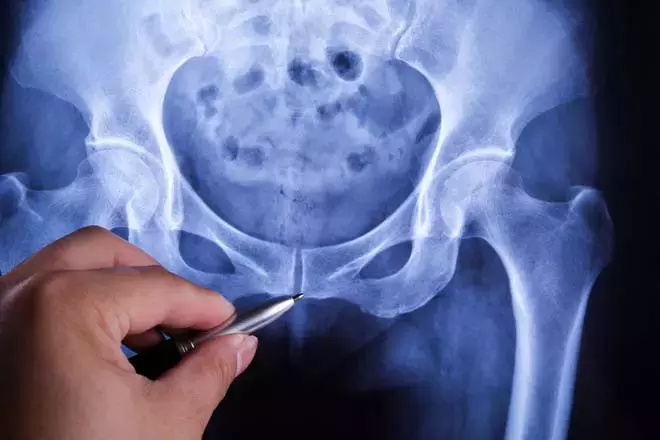

3. Kuyruk sokumu

Primatlardan miras kalan kuyruk sokumu, denge ve kuyruk desteği sağlardı. Bugün modern yaşam ve düz zeminler, bu kemiğin işlevini azaltıyor. Araştırmalar, kuyruk sokumunun zamanla küçülüp yok olabileceğini gösteriyor.